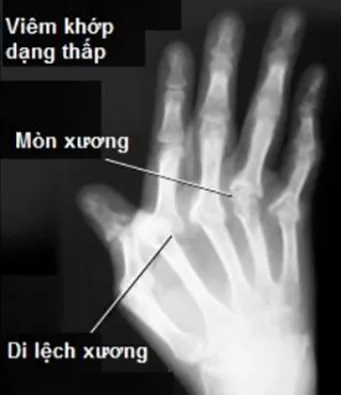

• Viêm khớp dạng thấp nặng ảnh hưởng đến cột sống cổ.